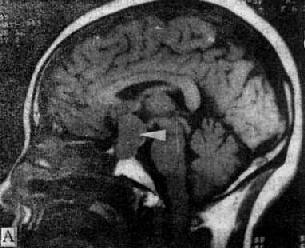

图5-1-6 MRI扫描SE序列图像

在矢状面(A)和冠状面(B)T1WI可见垂体肿块向鞍上延伸,呈等信号区(→);在横断面T1WI(C)和T2WI(D)上分别可见左枕和右基底节区脑梗塞灶呈低和高信号区(→);在矢状面T1WI(E)和横断面T2WI(F)上,可见基底动脉瘤环形影,其内为低信号和高信号区,高信号区为瘤内血栓形成(→)